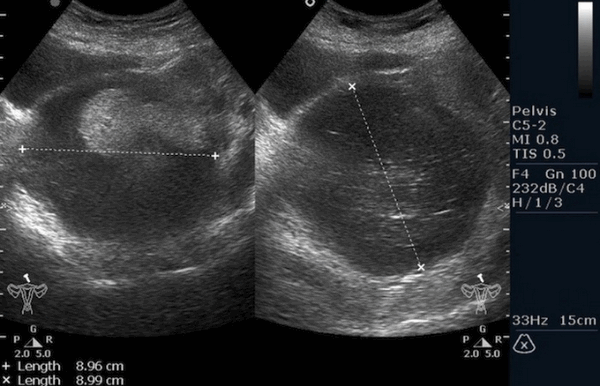

Рисунок 3. - тератома яичника а -УЗИ, б — МРТ.

- УЗИ. «Ультразвук» нужен для того, чтобы выявить первичный очаг как гонадной (в половых органах), так и внегонадной герминогенной опухоли. Его также проводят в ходе терапии, чтобы оценить ее эффективность.